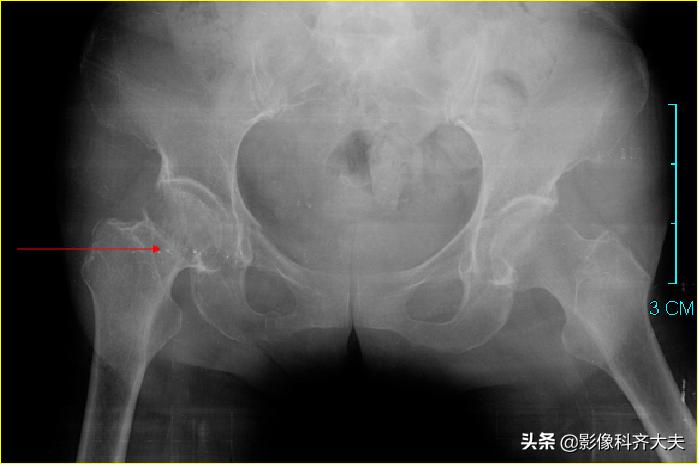

股骨颈嵌插骨折:老年人多见,断端常有错位或嵌入;可发生于股骨头下、中部或基底部;股骨颈短,肢体短缩,歪戴帽征;头下骨折引起关节囊损伤,影响血供,使愈合缓慢,甚至发生缺血性坏死。

股骨颈骨折伴有嵌入